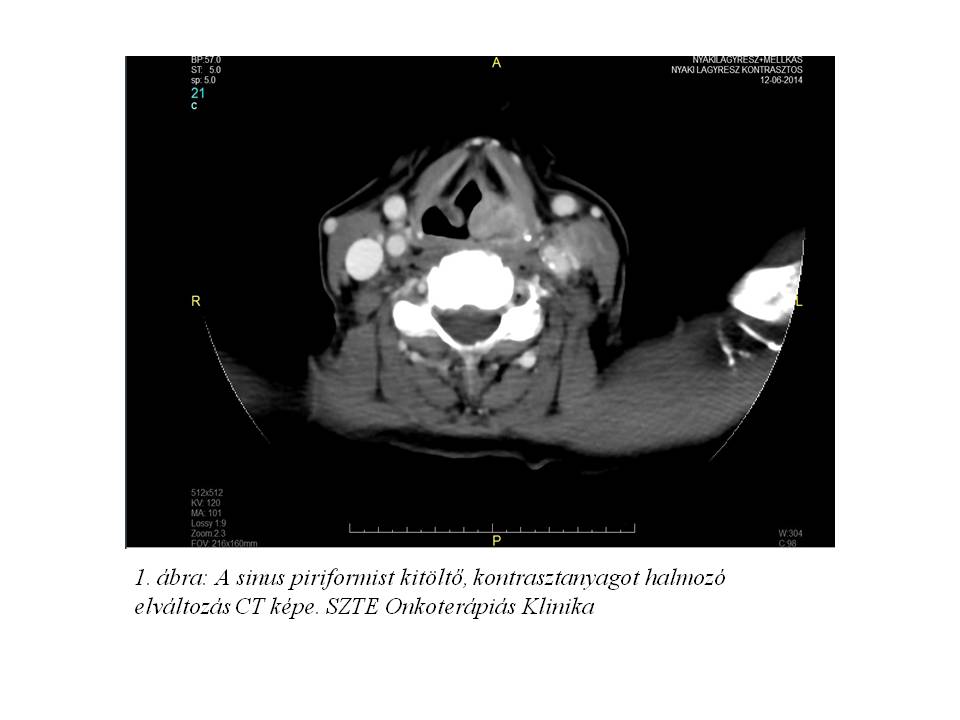

Esetismertetés: Jelenleg 52 éves, 30 éve dohányzó (napi 10 szál cigaretta), alkoholt nem fogyasztó, 20 évvel ezelőtt gyomorfekély miatt műtéten átesett, jelenleg hypothyreosissal kezelt nőbeteg esetét ismertetjük. A beteg 2014 júniusában jelentkezett fül-orr-gégészeten két éve tartó gombócérzés, időnként tapasztalt nyelési nehezítettség és fájdalom, a nyak bal oldalán 1 éve észlelt fájdalmatlan, kemény csomó, 2 hónap alatti 10 kg testsúlyvesztés, és 1 hónapja tartó, antibiotikus kezelésre nem szűnő, a bal fül felé sugárzó torokfájdalom miatt. Fizikális vizsgálat során a fejbiccentő izom elülső széle mentén a parajugularis régióban 2,5 cm átmérőjű, mobilis, ép bőrrel fedett nyirokcsomót észleltek. Rhino-pharyngo-laryngo-fiberoscopia során a bal oldali sinus piriformisban U-alakú, egyenetlen szövetszaporulat és nyálpangás igazolódott. Nyaki és mellkasi CT vizsgálat a hypopharynx régióban, a baloldali sinus piriformist kitöltő, a kontrasztanyagot homogénen és intenzíven halmozó, 20 x 14 x 20 mm nagyságú, a középvonalat meg nem haladó térszűkítő elváltozást, ebben a magasságban baloldalon a vena jugularis internát komprimáló, 20 mm átmérőjű, nekrotikus bennékű metasztázist, valamint a C.II csigolya szintjében dorsalisan egy 2 cm-es, patológiás szerkezetű nyirokcsomót írt le (1. ábra, 2. ábra). A tüdőkben metasztázisra utaló eltérés nem volt (T3 N2 cM0 stádium). Laryngomicroscopia során a bal oldali pharyngo-és aryepiglotticus redőn, illetve a sinus piriformis medialis falán elhelyezkedő teriméből szövettani mintavétel történt, mely közepesen differenciált laphámcarcinomát igazolt. Indukciós TPF kemoterápiát (docetaxel-cisplatin-5-fluorouracil) indítottunk, melynek 1. ciklusát követően a tapintható nyirokcsomó metasztázis eltűnt, a beteg nyelési fájdalmai megszűntek. A kemoterápia harmadik ciklusát követően fül-orr-gégészeti vizsgálat során makroszkópos tumor nem volt látható, az elvégzett PET/CT vizsgálat során FDG-avid malignitás nem igazolódott (3. ábra, 4. ábra). Jelenleg a beteg definitív sugárkezelését végezzük.